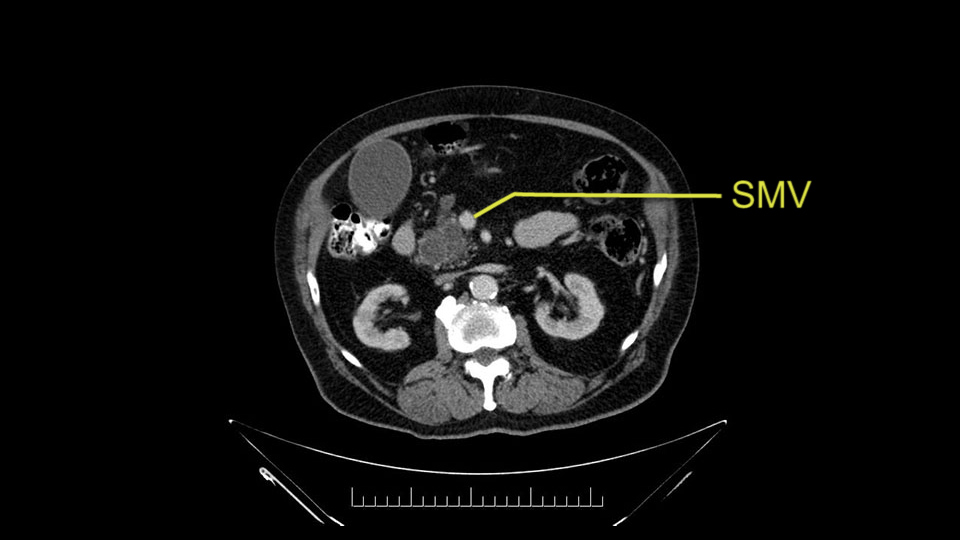

The next item that I would look at: the issue would be the vessels and usually start at the portal vein, watch the portal vein, follow it down, down-down-down to the neck of the pancreas - which is here - and there’s no impingement by tumor, which is great. The SMV and the splenic vein, which is here. The splenic vein junction is normal, which is great.

Then look at the first jejunal branch - which is this thing here - this little branch which goes under the SMA. It’s something that we’ve just started appreciating over the past few years and the reason for that is: there’s two or three small branches that come out of the uncinate into the the first jejunal and it’s a fairly inevitable part of the operation where there’s some bleeding. As long as you’re cognizant of what’s happening, it’s no reason to panic and that kind of bleeding will eventually stop or can be stopped but it’s not easy because these little vessels are fragile from the uncinate to the first jejunal. So I do focus on that and it’s pretty consistent I’d say 9 times out of 10, people have that first jejunal.

The initial hepatic flexure mobilization and the Kocher procedure is then going to enable me to understand the uncinate process of this patient, which should not be a problem, again. But the initial pictures had shown a degree of touching. I would not even say involvement or abutment; a degree of touching with the superior mesenteric vein. So that would give me an early chance to assess how the superior mesenteric vein is in this patient. So this would be the initial slowing down moment.

The next thing we always evaluate, although we do not expect invasion to the portal veins in this case, we must always trace the path of the portal vein, in both directions, from top to bottom. The splenoportal confluence and the superior mesenteric vein, which in this case does not appear to be compromised.

The first steps of a pancreaticoduodenectomy involve ensuring the CT findings are correct: exploring for signs of metastatic disease, peritoneal implants involving the omentum or the undersurface of the diaphragm and if again this is confirmed exploration that there's no metastatic disease, I begin the mobilization and really determining the relationship of the tumor with the major visceral vessels. I start by an extended Kocher maneuver, identify the superior mesenteric vein below the neck of the pancreas. They’re very thin walled vessels and as you're dissecting you have to use the ultimate care and meticulously dissect the superior mesenteric vein, ligate the anterior branches and begin the dissection from below to under the neck of the pancreas. At this point, if there's no reason to be concerned about whether there is any vascular invasion below, I usually take the gallbladder down. I mobilize the common hepatic duct above the insertion of the gallbladder. This patients already has a stent in place. So I would divide the bile duct at this point. This facilitates the dissection of the anterior surface of the portal vein and as I would expect looking at this imaging that there is nothing to be concerned about in terms of vascular involvement.